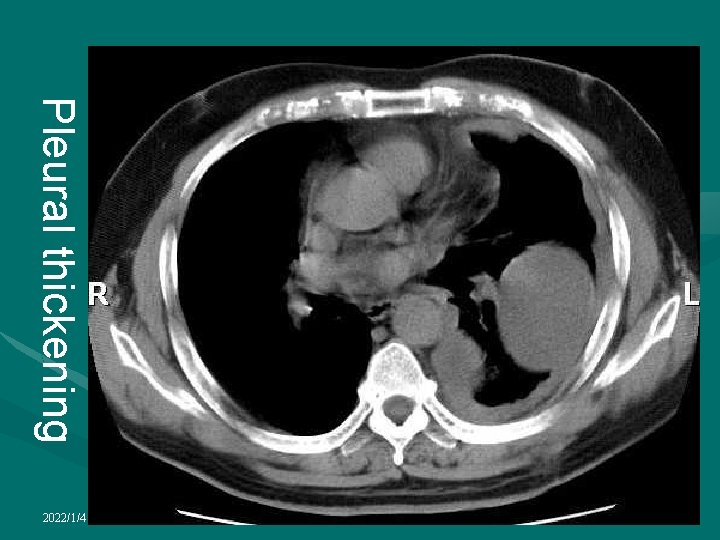

Pleural thickening • May follow organization of a variety of inflammatory processes involving the pleura • Include infective pleural effusions, empyema, hemothorax, occupational exposure to asbestos or talc, rheumatoid lung disease, radiation therapy and drugs • May also occur as a result of infiltration of the pleura by various malignant tumors, especially mesothelioma and metastatic adenocarcinoma • May be uni- or bilateral, diffuse or localized and may be calcified 2022/1/4

Pleural thickening • On the chest radiograph the changes predominantly affect the dependent areas with blunting of the costophrenic angle • Extensive pleural thickening produces volume loss and a veil-like reduction in transradiancy of the hemithorax • There is a soft tissue density medial to and paralleling the chest wall with a well-defined inner margin • There may be extension into the fissures which appear thickened 2022/1/4

Pleural thickening • CT is much more sensitive in detecting pleural thickening which is seen as a layer of soft tissue density between the chest wall and lungs • Thickening of as little as 12 mm can be detected with HRCT • best assessed immediately internal to the ribs where there is normally no detectable soft tissue • Between the ribs the normal pleura and innermost intercostal muscle produce a thin line which should not be mistaken for pleural thickening • In the paravertebral region, any thickening of the pleural line is abnormal • In many diseases causing pleural thickening the layer of extrapleural fat between parietal pleura and chest wall is increased, allowing a subtle degree of thickening to be detected, especially with HRCT 2022/1/4

Pleural thickening • The distribution and shape of pleural thickening as determined by CT are useful for differentiating between benign and malignant causes of pleural thickening • The most useful signs in predicting the presence of malignancy are circumferential thickening, nodularity, thickening of greater than 1 cm and involvement of the mediastinal pleura • Localized pleural thickening often occurs at the lung apices with increasing age, forming an apical cap • This may be uni- or bilateral and is usually of homogeneous, soft tissue density, usually less than 5 mm thick, with a well-defined inferior margin 2022/1/4

Pleural thickening 2022/1/4